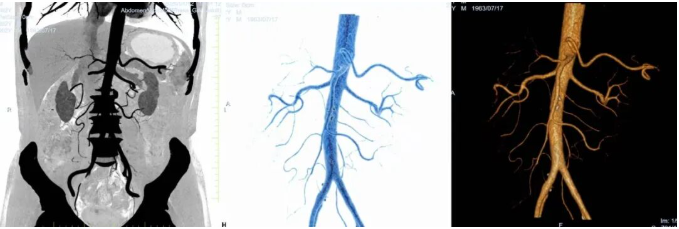

血管三维重建CT更揭示出一例复杂变异:肝总动脉与胃十二指肠动脉共干发自肠系膜上动脉主干右前侧,肝总动脉向上供应全肝,胃十二指肠动脉则走行于胰头后方,成为该区域主要血供来源。此类变异极大地增加了手术分离的难度与风险,稍有不慎即可能导致大出血或脏器缺血。

*血管三维重建CT影像图